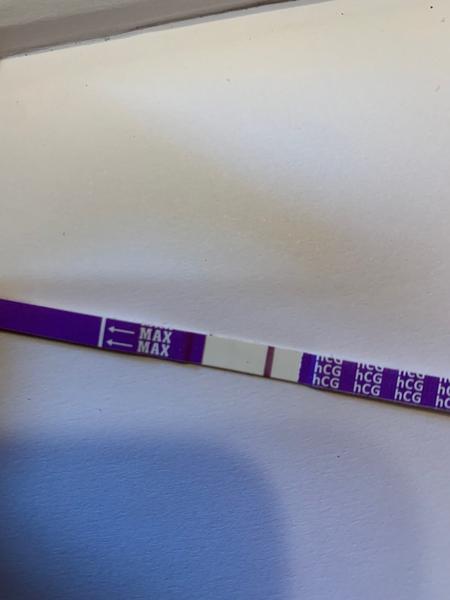

Zdravím, prosím o vaši nynější zkušenost s testy Dr.Max. Během let se jejich kvalita měnila několikrát. Jsem nyní 34.dc tj cca 4dny meškání os obvyklé MS. V tomto cyklu jsem 17. a 18.cd špinila, ale kdy byla ovulace nevím. Dnes jsem si udělala test a po celý limit byl bílý. Pak cca po 1,5hod jsem ho šla vyhodit a je na něm toto. Máte zkušenost s ryskami u tohoto testu po limitu? Děkuji

Děkuji, také jsem právě brala test jako jasně negativní, když do 10min nic neukázal. Ale až po takové době jsem objevila ve skutečnosti hezky viditelnou čárku (do růžova je, zkusím ještě lépe vyfotit). Zkusím ještě další test třeba zítra nebo pozítří..🥴

@vnikan tyto testy mi většinou dělaly rysky, co se objevily po 10 minutách, takže jsem to nebrala. Ale když tam opravdu čárka byla, objevila se hned. Sice hodně slaboučká, ale hned. Ovšem nešla takhle pěkně vyfotit, jako tvoje. Takže si vlastně neporadím 😅 ale budu držet palce, ať to dopadne 😊

@vnikan na začátku se může objevit čárka i po limitu ,prostě je to pozitivní,zkuste obden další tt,čárka musí sílit

Byly nejlepsi a kdyz ukazal ducha, tehotna jsem byla. Ale tohle vypada jako ryska